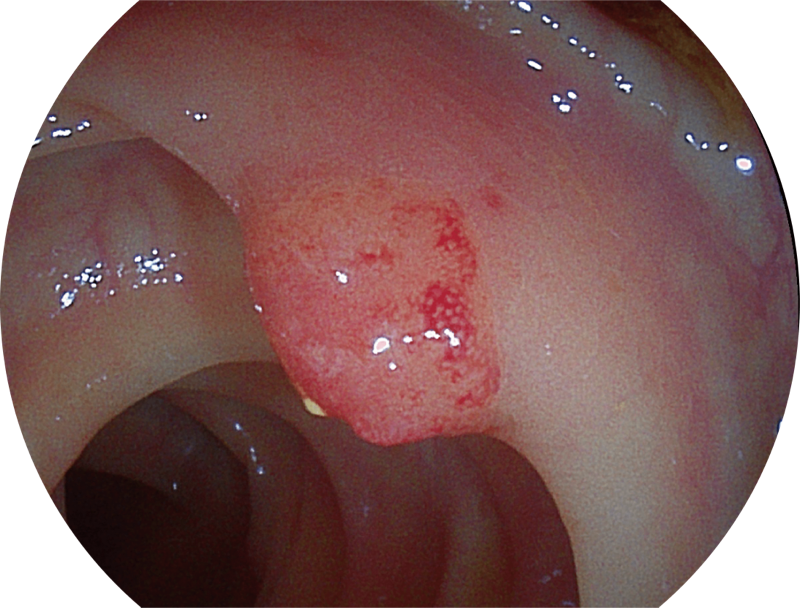

光电复合染色成像

(Versatile Intelligent Staining Technology)

能够凸显黏膜浅层血管轮廓和黏膜表面微结构,适用于中、近景观察下的早癌精确诊断。